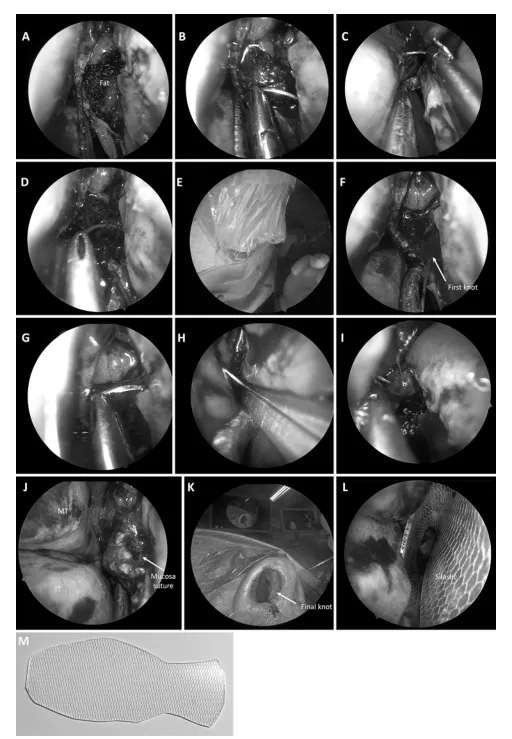

图2. 显示手术缝合步骤的照片。

A:手术腔用脂肪填充,并涂抹胶水。B 和 C:从右鼻孔,缝线被固定于粘膜瓣的下部,用脑垂体钳将针从外侧粘膜瓣穿至鼻中隔,从对侧鼻孔引出。D:然后,再次将针穿过鼻中隔,从内侧粘膜瓣穿出,再引出体外。E 和 F:通过在外部沿同一方向打三个简单的结,使其滑动至粘膜切口的边缘,从而获得紧密缝合。G-J:沿粘膜切口的全长重复步骤B-D,以获得紧密缝合。IT = 下鼻甲;MT = 中鼻甲。K:一旦切口完全缝合,将同侧鼻孔的针引至表面,并使用标准持针器穿过前庭鼻中隔的粘膜。在持针器上绕两圈,在最后一个进针点之前用持针器尖端抓住缝线形成一个小环来打结,然后用两个额外的结加固。L:沿鼻中隔放置一块硅胶片以加强缝合。M:裁剪成鱼形的硅胶片照片。

图4. “筷子”技术照片。

A 和 B:术者非利手握持内镜和可旋转可塑吸引器,同时利手使用另一器械(A图中为磨钻,B图中为双极电凝)。C:内镜被轻轻支撑在食指和拇指之间的空间,允许指尖操控吸引器并在拇指和其他手指间滚动吸引器的旋转部件。